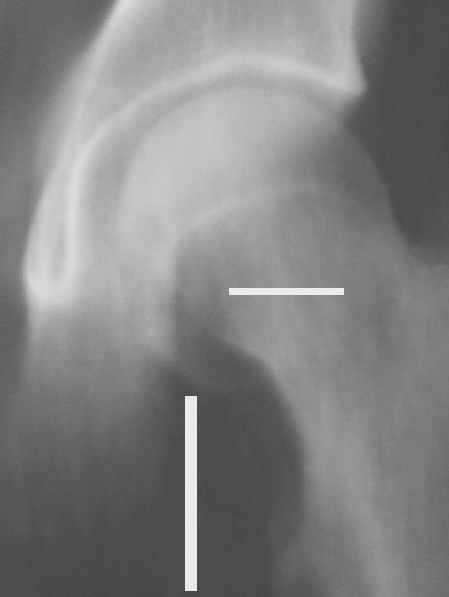

Уважаемые коллеги! Заканчивая обследование больного с переломо-вывихом бедра сделал ему обычные R-томограммы. Кажется удалось "поймать" и отломок и донорское место. Мои выводы - в скиаграмме. Считаю, что это передне-нижний фрагмент головки, образовавшийся вследствии отрывного перелома. На томограммах отломок обозначаю длинной стрелкой, а место откуда он оторвался - более короткой. Учитывая тот факт, что его размеры по КТ 25 х 15 мм считаю, что его фиксация на место необходима для профилактики артроза, что при 16-ти летнем возрасте пациента важно в плане максимального отодвигания эндопротезирования. Планирую оперировать его 24.05.05 г. Результаты представлю.

Прямой при поступлении

Несколько соображений к "картинкам". На прямом снимке и КТ-томограммах все типичные линии вертлужной впадины: крыша, передняя стенка, задняя стенка - сохранены. На КТ-сканах 6 и 7 появляется фрагментация головки. С учетом R-томограмм отломок расположен спереди-снизу, а не сзади-сверху от сустава, как написано в описании КТ.